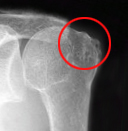

診察、X線(レントゲン)、超音波エコー、MRIを行います。

X線(レントゲン)所見では、肩峰や上腕骨の変形や、肩峰と骨頭間距離などにより評価をします。